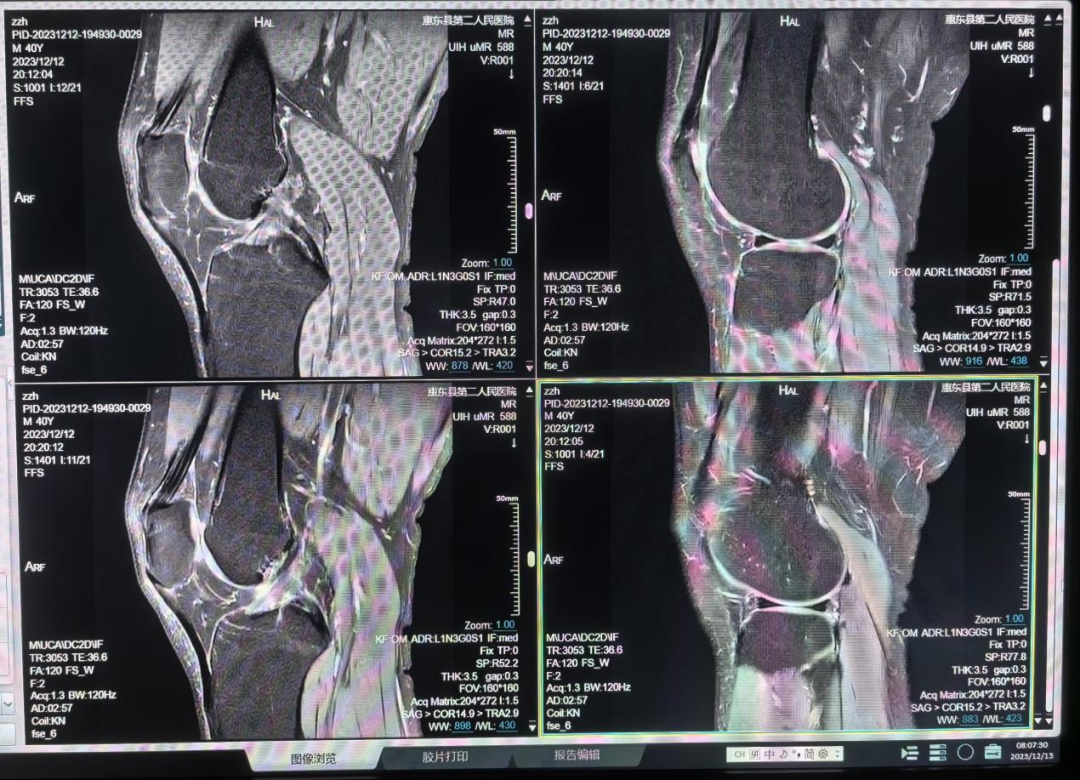

骨关节和肌肉MRI检查

骨关节创伤;骨关节肿瘤与肿瘤样病变;骨髓病变;类风湿关节炎;强直性脊柱炎;股骨头缺血坏死;全身肌肉软组织损伤或病变;肌肉软组织肿瘤。

膝关节半月板损伤磁共振成像